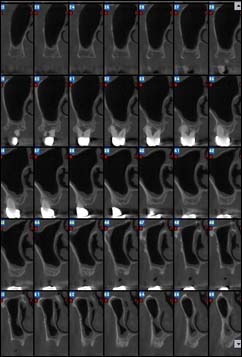

Reconstruction panoramique